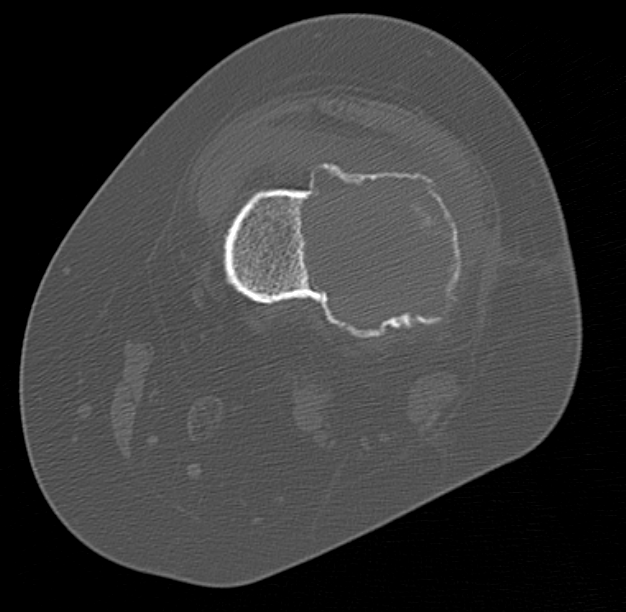

X-ray

Eccentric, sharply demarcated lytic lesion

- no sclerosis around lesion

- narrow zone of transition

- metaphysis, extending into epiphysis

- no mineralization

CT